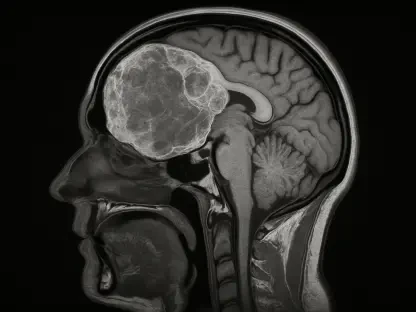

The promise of enhanced diagnostic accuracy is a primary driver behind the seventy-four percent of physicians who express optimism about the current technological landscape. Machine learning models are now capable of scanning radiological images, pathology slides, and genomic sequences with a level of consistency that complements human expertise. These tools do not replace the radiologist or the oncologist; rather, they serve as a rigorous second set of eyes that can flag subtle anomalies that might be overlooked during a long shift. By identifying patterns in massive datasets that are invisible to the naked eye, artificial intelligence helps in detecting chronic conditions or aggressive diseases at much earlier stages. This proactive approach to diagnosis is fundamentally changing the prognosis for many patients, as interventions can begin long before symptoms become severe, thereby improving the overall quality of life and long-term survival rates.